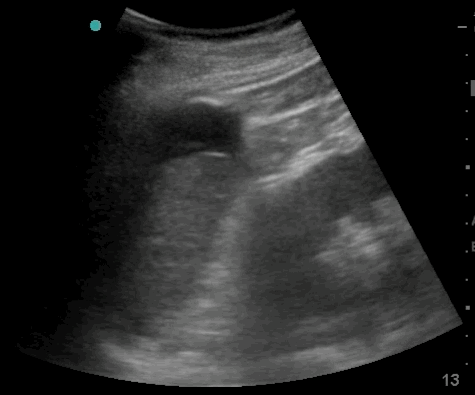

22_Abdomen_LUQ_Perisplenic

Free fluid between diaphragm and spleen. Further fluid is seen in the pleura.